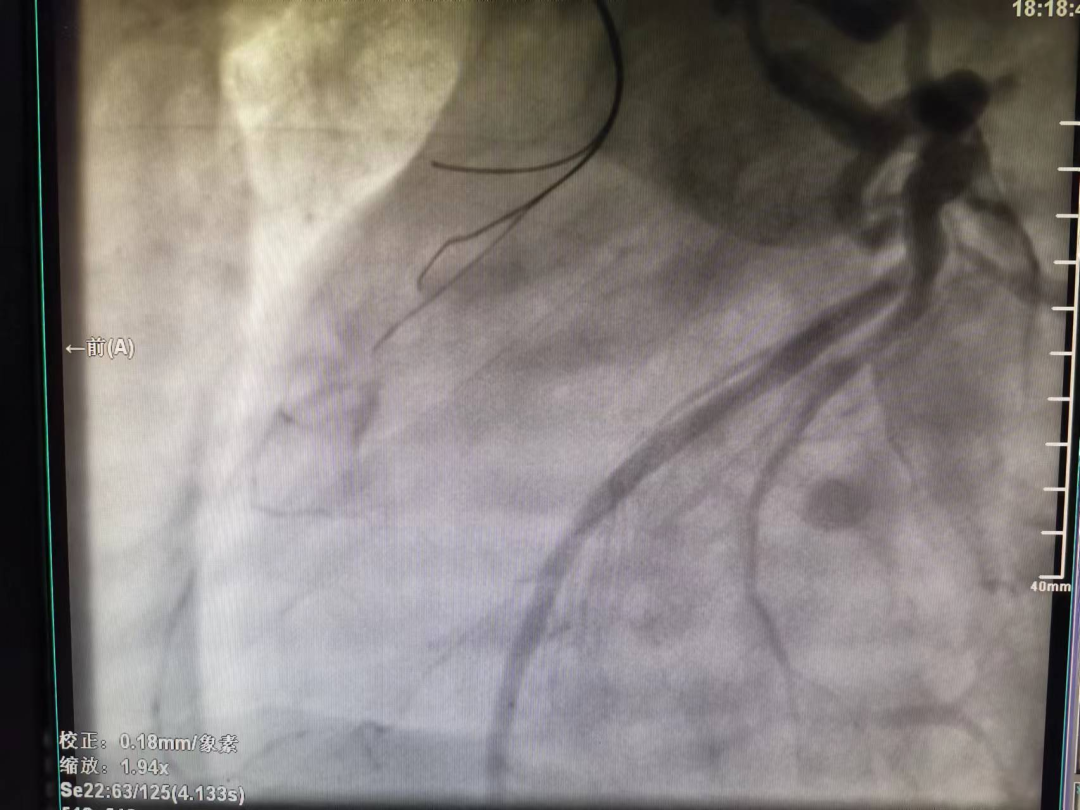

37岁的陈先生,因“胸闷、胸痛4月,加重10天”于11月1日收入我院心血管内科病区,从心电图及心脏彩超结果分析,患者具备冠脉造影的强适应征。郑涛副主任医师仔细查看病人,询问病史、症状,结合体征、检查结果,建议行冠脉造影术,并详细解释手术过程、风险,打消患者顾虑。2022年11月04日行冠脉造影术:术中穿刺右侧桡动脉后造影导管顺利进入左冠脉,造影示左冠状动脉先天性冠状动脉瘘,并可见左冠向右冠远端的逆向血流,而因患者主动脉弓异常扭曲,常规造影导管及专用右冠造影导管反复尝试多次均无法找到右冠脉开口,考虑患者的右冠状动脉开口变异,遂使用猪尾巴导管链接高压注射器造影后隐约显示右冠开口位置,因造影耗时近2小时,为保证患者安全,暂时先下台,准备再次择期手术。

左冠脉造影显示左冠向右冠远端的逆向血流